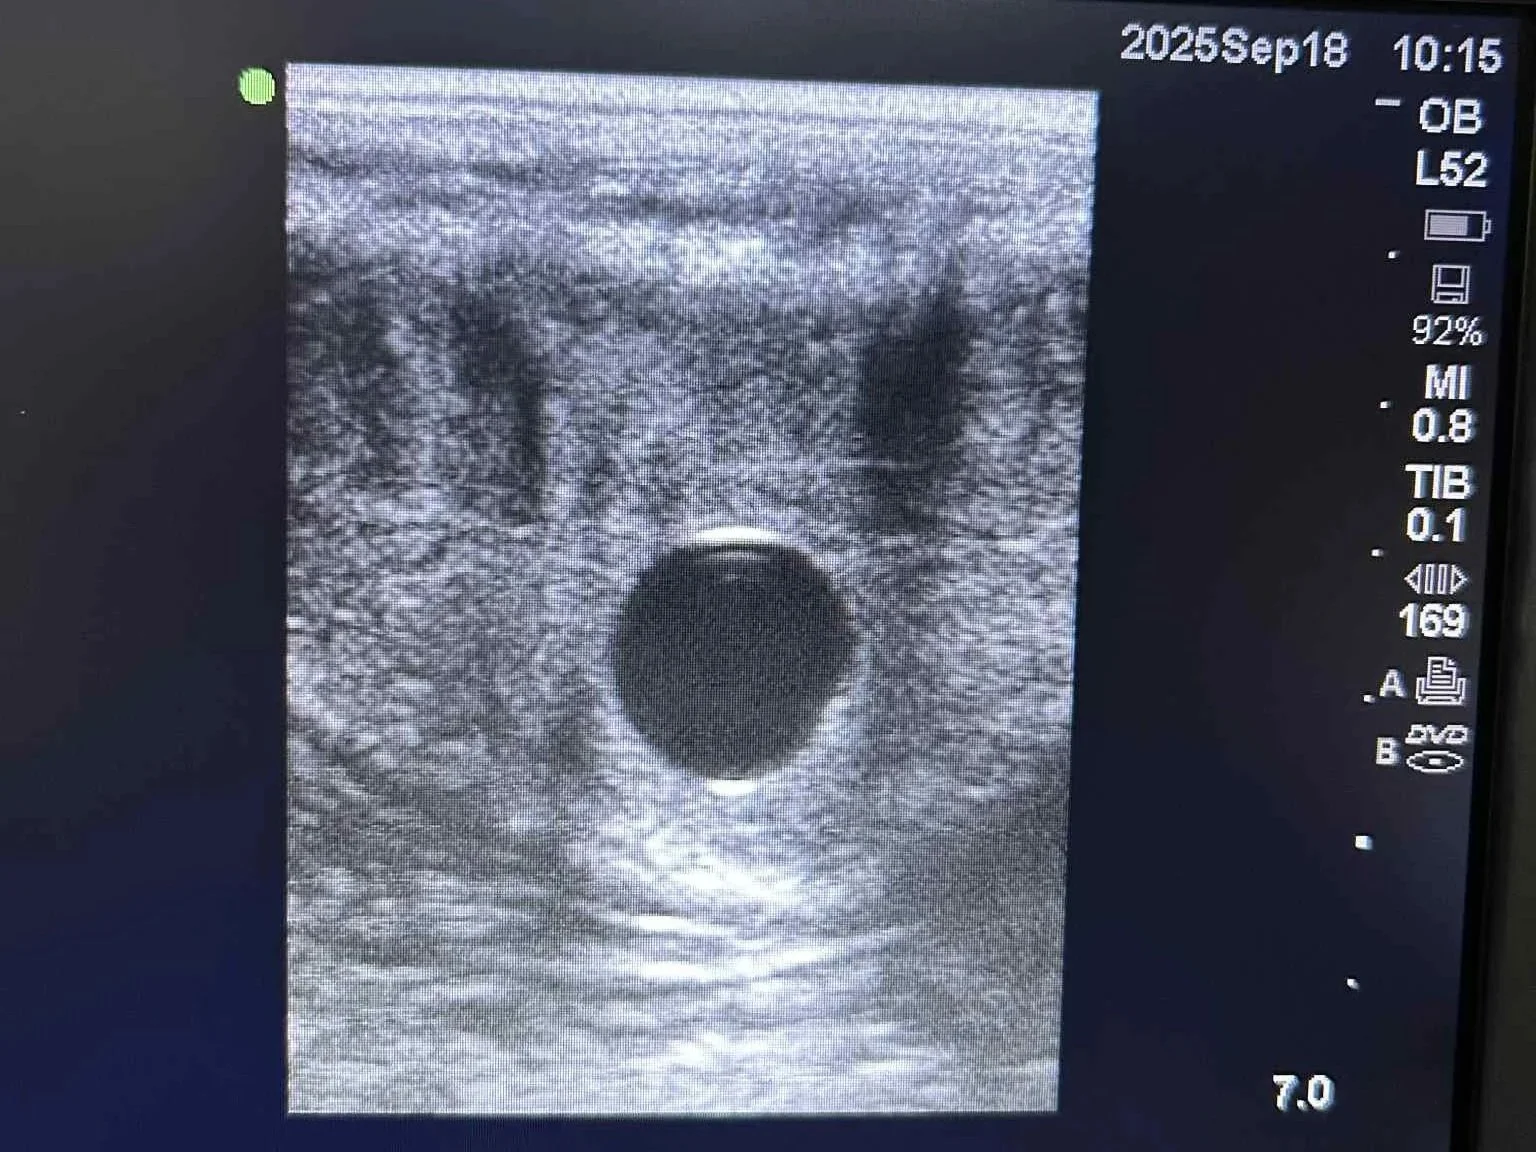

He kicked off the week at Woodlands with the honour of the first positive scan of the breeding season.